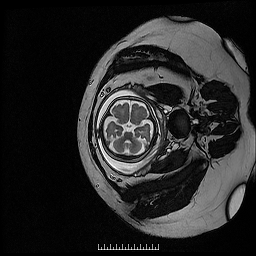

1.胎儿MRI扫描:胎儿成像的首选检查手段为超声,其操作简单,无创,快速,实时,价格低廉,特别适合大范围人群筛查,但也有不足之处,如超声难以穿越胎儿颅骨,视野偏小,对母体肥胖,有子宫肌瘤,羊水过少,多胎等情况时,对胎儿显示效果欠佳。磁共振则不受到这些因素影响,对羊水过少,双胎,及孕晚期胎头入盆或胎儿颅骨骨化,胎儿磁共振可以起到明显的补充作用。